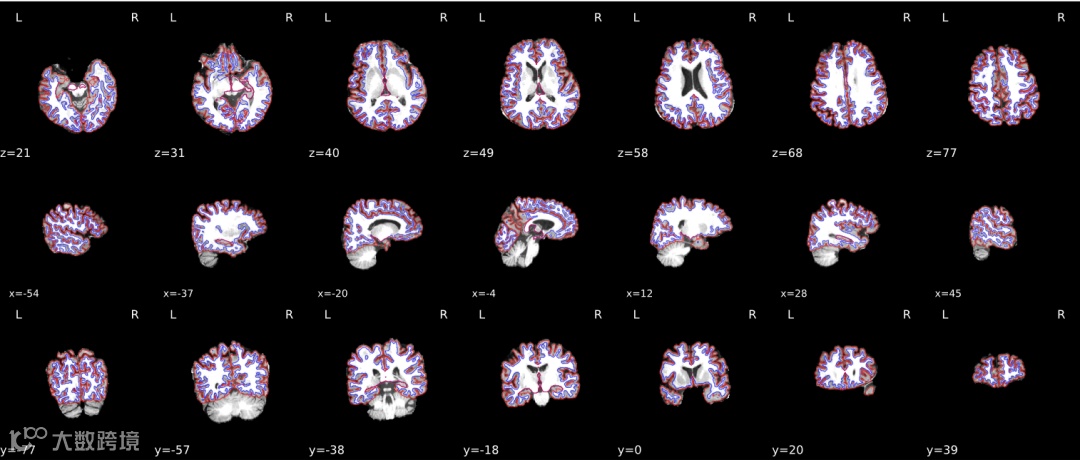

结构像(sMRI):提供标准化 sMRI 流程(含皮层厚度/体积计算、配准与分割),参数与版本自动留痕。

后处理:皮层厚度与皮层/皮层下体积、静息态/任务态网络、白质纤维束追踪与网络拓扑、ROI 与全脑两种颗粒度可切换;模块可自由组合。

统计与可视化:内置常用统计(组间比较、相关、回归)与多模态融合;自动生成脑区着色图、网络图、3D 脑模型与标准化报告,便于论文素材与临床沟通。